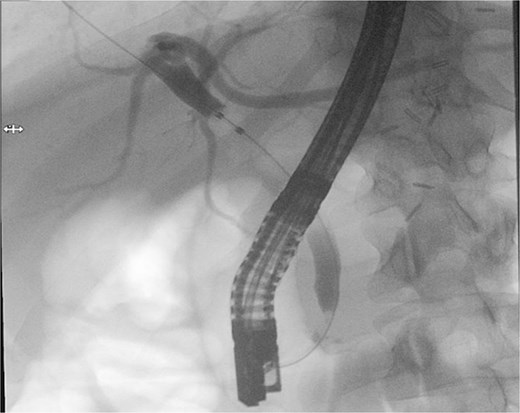

Patient subsequently performed endoscopic retrograde cholangiopancreatography with needle-knife cannulation. Cholangiogram confirmed a distal CBD filling defect. A sphincterotomy and balloon sweep were performed, successfully extracting stones, and an 8.5 Fr × 7 cm stent was deployed (Fig. 3, Fig. 4).

Endoscopic retrograde cholangiopancreatography fluoroscopic image showing contrast opacification of the biliary tree with a distal common bile duct filling defect, consistent with choledocholithiasis.